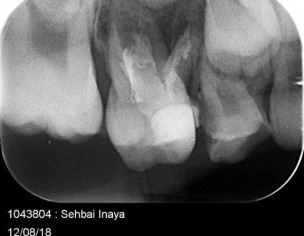

My daughter is 7 and hav deep cavity I took her to dentist one said she need 1 extraction and when I went to pediatric dentist she said she needs 4 extractions which she is going to do altogether same day I am attaching her xrays can any dentist plz advise after looking at the xrays thanks

Her both upper D are definitely for extraction and for her E need to evaluate clinically as well there might get b some Endodontic treatment and space maintainers afterwards

After extraction she will need space maintainer to keep first molar in its place so better to go for RCT to keep this tooth till age 12

Observe .Do symptomatic i advice endodontic treatment..